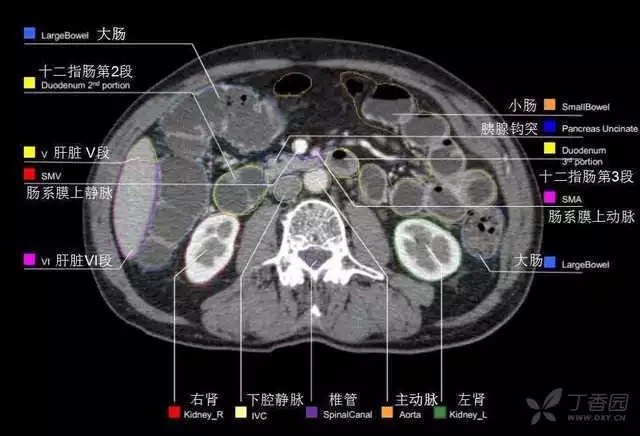

腹部肝脏高清CT断层的图谱

全腹部高清CT图谱,淋巴结彩色图谱,血管解剖图谱大汇总!

超声肝脏分叶及分段

肝脏分段和基本解剖学标志